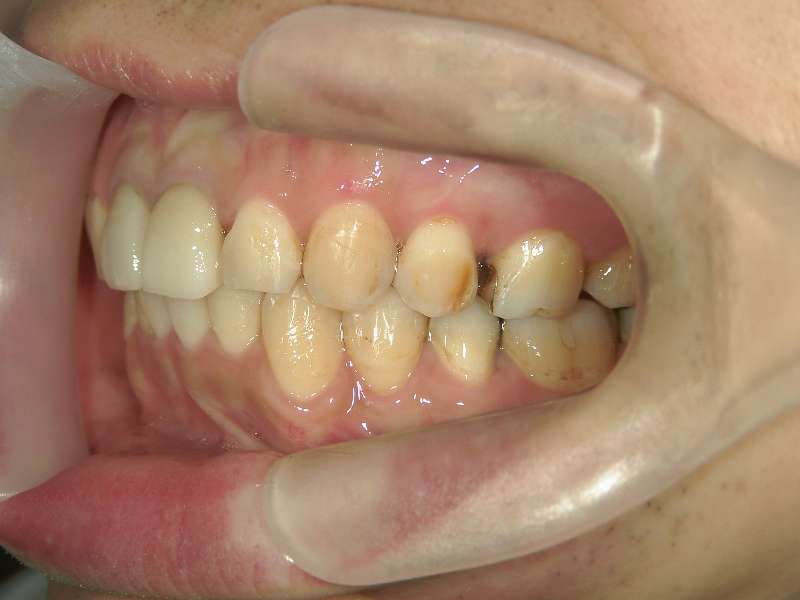

33歳男性 浜松市東区在住

治療期間1年7ヶ月

主訴:前歯の歯並びが気になる。

矯正歯科 治療前 上顎の左右4番計2本を抜歯し叢生を改善。